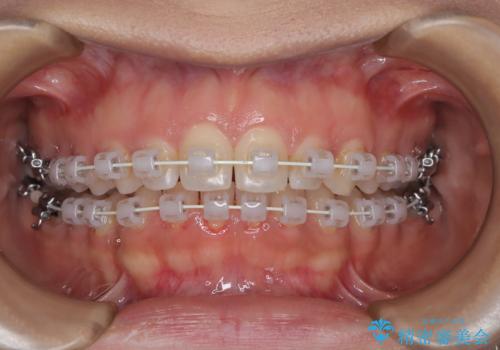

本症例では、非抜歯での治療を選択したため、スペースを確保するためにIPR(歯間削合)を行い、歯列を整えました。オーバージェット(上の前歯と下の前歯の水平的なズレ)は残る結果となりましたが、見た目や機能の改善を重視し、患者様と治療計画を共有しながら進めました。治療中は、歯列全体のバランスと噛み合わせを考慮しつつ、矯正装置の適切な使用を徹底しました。当初の計画通りに治療を完了し、患者様にも満足していただけました。